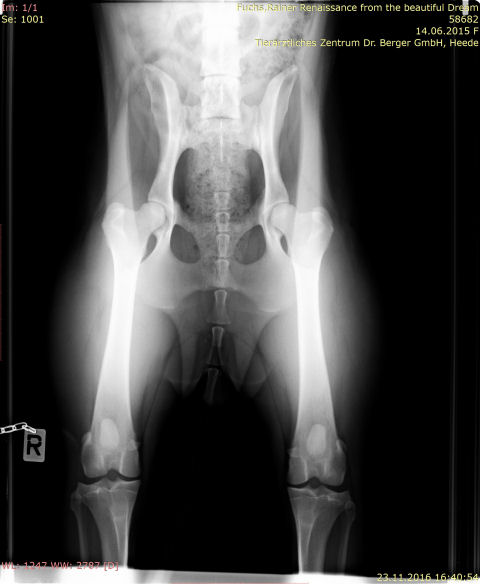

HD-Hüftgelenksdysplasie

roxy-HD-seite a

roxy-HD-seite b

IMG-0003-00001-hüfte-roxy